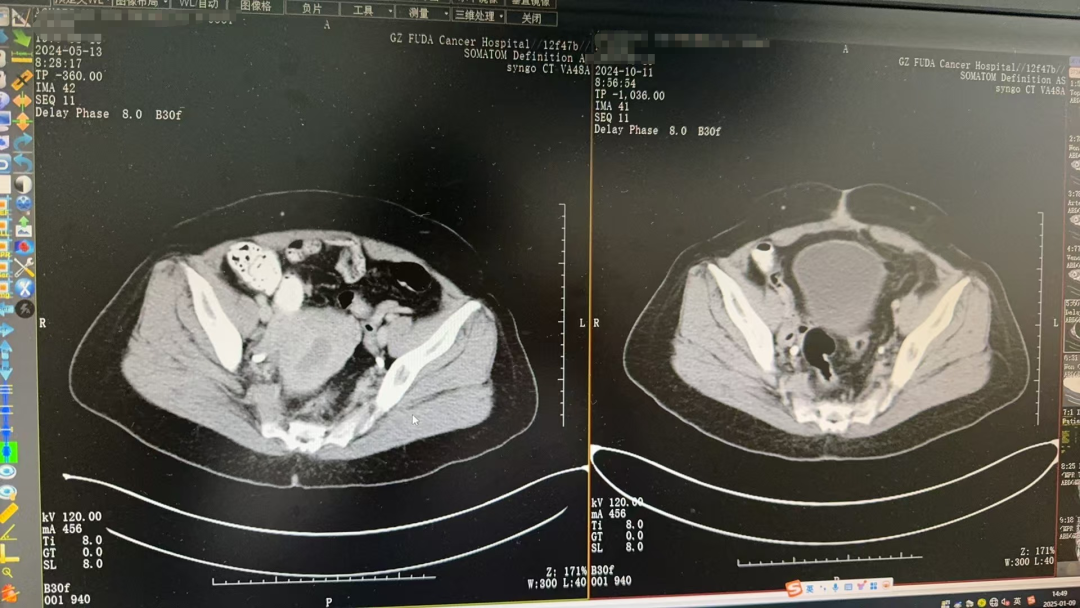

“考虑肿瘤是早中期,首选治疗以手术切除为主。”结合Agustian入院后及既往检查结果,临床诊断为子宫内膜癌2期。经过多学科讨论和评估后,Agustian接受了开腹广泛子宫切除术+双侧附件切除术+盆腔淋巴结清扫术。术后结合临床和免疫组化结果显示,病变符合子宫内膜样癌,肿瘤从颈管内口至子宫体部,范围约9×6×5cm,已侵及深肌层,侵犯深度约1.3cm。

△左图为治疗前,右图为手术后影像

为减少复发转移,提高生存率,Agustian术后接受了多个疗程的辅助放疗。原本计划25次放疗,但在第15次放疗后,Agustian出现放射性肠炎。综合Agustian全身情况,其主管医生卓茜建议暂停放疗计划,后续以定期复查为主。目前Agustian身上除放疗带来的一些副反应外,没有其他不适,总体恢复良好。